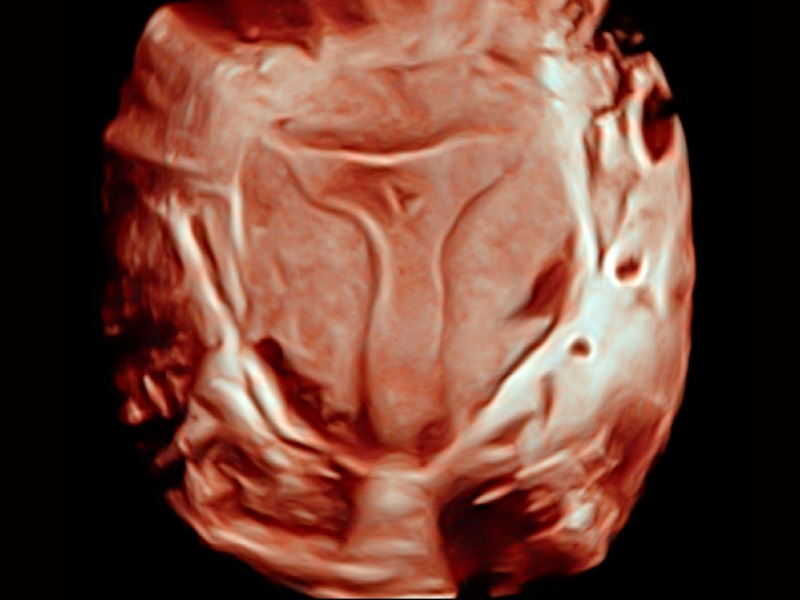

• 光影成像

三维光影成像技术采用新型的渲染方式,增强边缘信息,使得轮显示清晰完整,为临床提供丰富、直观的三维结构,提供临床诊断准确性。